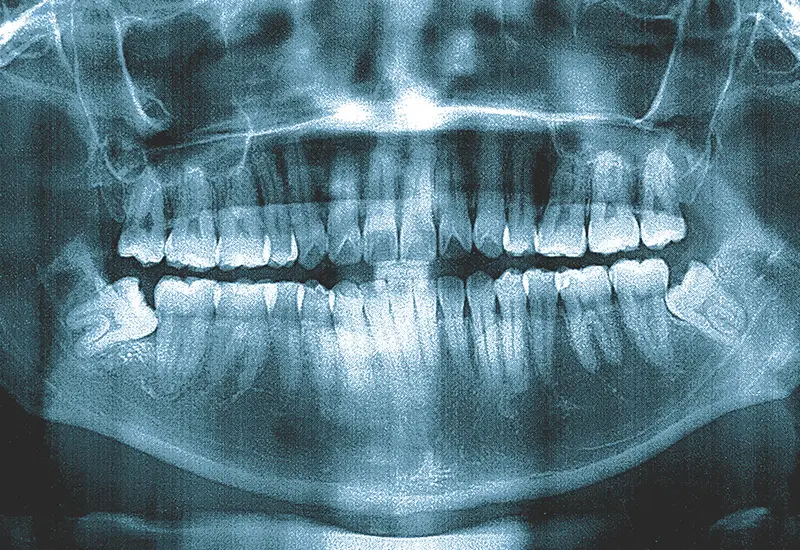

住吉区の歯医者 松岡歯科・矯正歯科では、皆様のお口の健康をサポートするために、虫歯や歯周病の治療から矯正歯科、インプラントまで幅広く対応しております。

こちらページでは、当院で行っている診療を紹介しております。